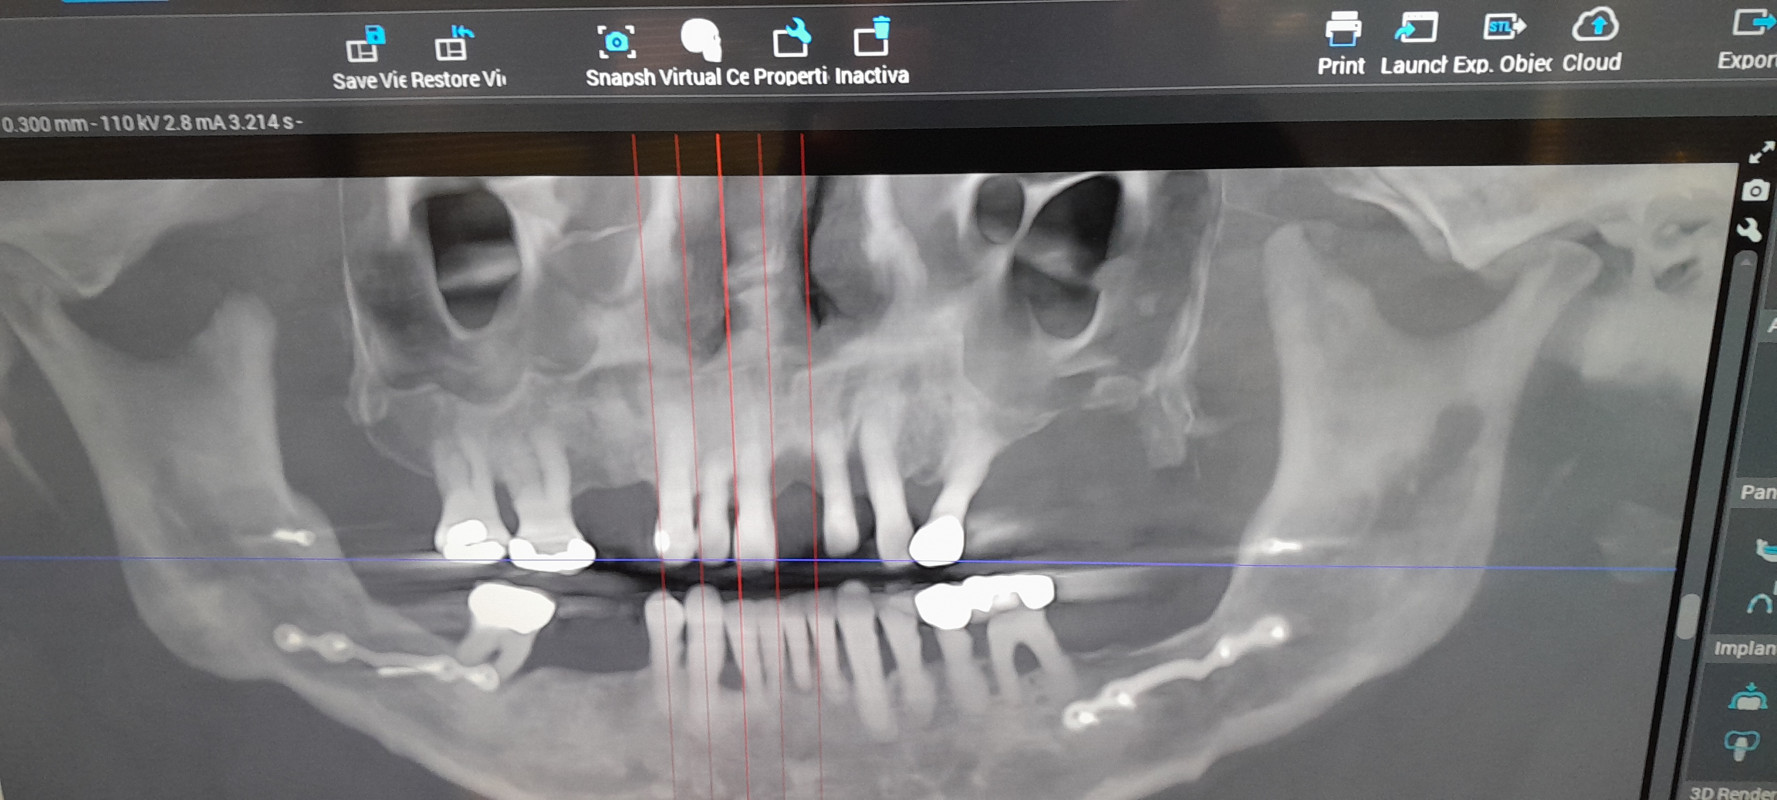

hello i am raising funds for a full mouth restoration top and bottom arches. i am retired 71 y.o. with osteoarthriyis bi lateral knee replacements heart stfnt patient 2 years post surgery living on a meager income and cannot afford this dental procedure as my reason for being here at helping hand. i have several missing teeth and peridontal disease.(see attached scan) the MD and peridontist said that i need to have this done soon as possible due to the small multiple infections forming around my teeth risking the chance of septsis sètting in. i have tried to find financing to no avail due to my income level, leading me here. i must say im a bit embaressed to have to ask for financial help in this matter however i have exausted all other resonable avenues sometimes those in need have to swallow their pride and ask for a helping hand. i can never you all enough just try and know i am forever greatful and can only pass on a helping hand if im able to someone else who may be in need of something i can give. westher you choose to donate or not thank you for taking the time to read my plea for a helping hand >^,,^< sincerly forever greatful Lynrd